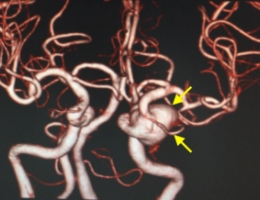

物が二重に見えるようになって発症した内頚動脈大型動脈瘤(矢印)の症例です。クリッピング術で直接動脈瘤をつぶすことができないため、バイパス術(矢印)を増設し内頚動脈を遮断することで動脈瘤を治療しました。